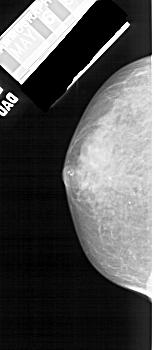

A_1517_1.RIGHT_MLO

RIGHT_CC LINES 3961 PIXELS_PER_LINE 1831 BITS_PER_PIXEL 12 RESOLUTION 43.5 OVERLAY

FILE: A_1517_1.RIGHT_CC.OVERLAY

TOTAL_ABNORMALITIES 1

ABNORMALITY 1

LESION_TYPE CALCIFICATION TYPE PLEOMORPHIC DISTRIBUTION CLUSTERED

LESION_TYPE MASS SHAPE ARCHITECTURAL_DISTORTION MARGINS ILL_DEFINED

ASSESSMENT 5

SUBTLETY 3

PATHOLOGY MALIGNANT

TOTAL_OUTLINES 1

BOUNDARY